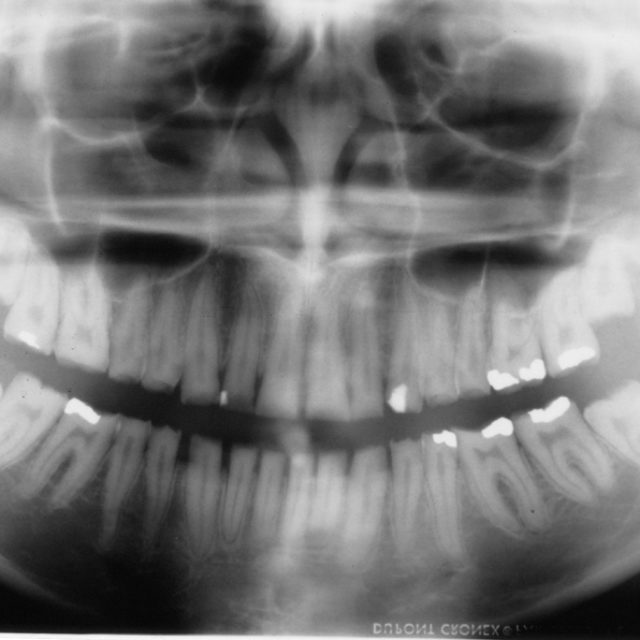

Hoy, miércoles 06 de diciembre de 2.017 en Salud y Bienestar El Dr. Alfredo Natera, odontólogo, director del Centro Venezolano de Investigación Clínica para el Tratamiento de la Fluorosis…

Hoy, miércoles 1 de noviembre de 2.017 en Salud y Bienestar El Dr. Tomás Seif, Odontólogo especialista en prótesis y estética dental, nos habla de los procedimientos dentales estéticos…

Hoy lunes 16 de marzo del 2015 en Salud y Bienestar: «Odontología estética y prótesis» con el Dr. Tomás Seif. Odontólogo / Especialista en Odontología Estética y Prótesis 212-992-02-42 tomasseif.com…